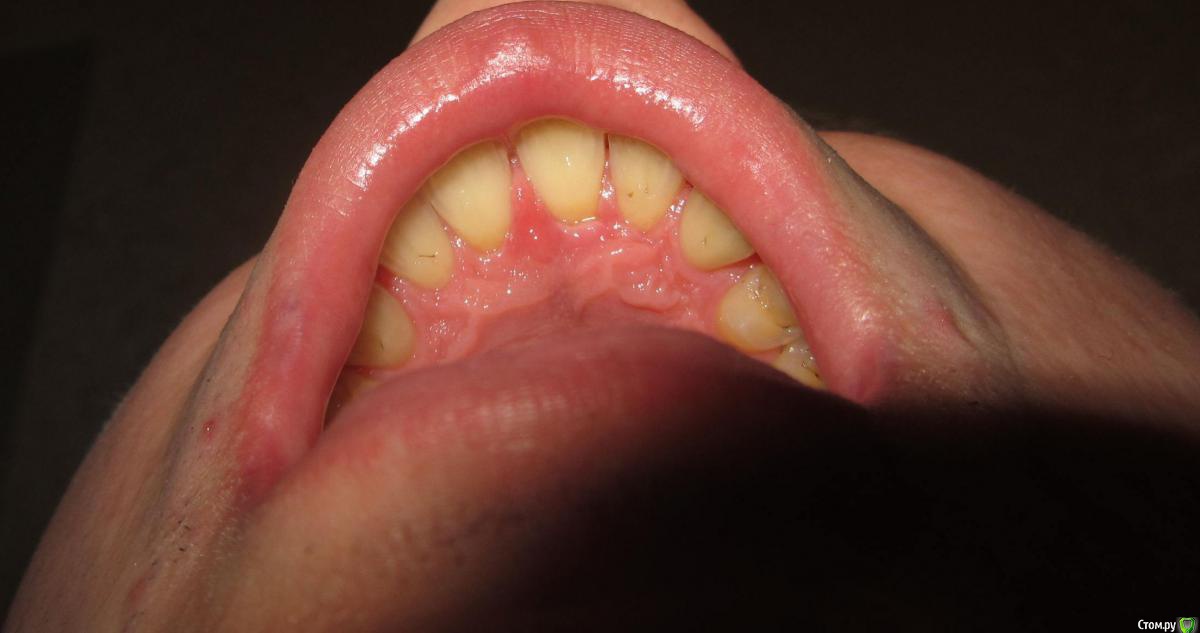

janis1 Опубликовано 14 ноября, 2015 Поделиться Опубликовано 14 ноября, 2015 Доброго времени суток, уважаемые профессионалы.Очень надеюсь на вашу помощь.Коротко о себе:37 лет, пол мужской. Так сложилось что в последнее время меня постигло сразу три проблемы,как мне кажется все они имеют между собой четкую связь. Основная проблема, с болями верхней челюсти, началась у меня около месяца назад. Боль не очень сильная, но практически постоянная. Боль не имеет какой-либо конкретной локации (болит именно вся челюсть). С утра она меньше, ближе к вечеру усиливается. В последнее время немного отдаёт в скулу. Одновременно с появлением боли, во рту, в районе дёсен, появился как бы привкус соды (немного похожий на вкус крови, но крови в ротовой полости нет).И в довершение всего начали катастрофически искривляются зубы верхней челюсти.На самом деле проблемы с прикусом у меня были уже с детства, примерно в 10 - 12 лет я носил пластинку для исправления прикуса.Но к сожалению лечение так и не закончил, соответственно прикус все это время у меня был неправильным, но до последнего времени он меня не беспокоил, так как был если так можно сказать "в пределах разумного", и в течении долгого времени был неизменен, но в последние несколько месяцев верхние зубы искривились настолько катастрофически что что я реально начал шепелявить. При попытке расшатывания зубы стоят крепко, не болтаются. Пока во всяком случае... Со всеми этими проблемами я пробовал обращаться к зубному хирургу и ортодонту,ни хирург, ни ортодонт к которым я обращался не смогли назвать каких-либо конкретных причин по которым может появляться боль в верхней челюсти и привкус во рту.Врачи к которям я обращался действительно хорошие специалисты, но похоже видят проблемы узко по своей специализации.Единственно хирург указал на то, что возможно придется удалять восьмерки, а ортодонт предложил установить брекеты на обе челюсти.Я прекрасно понимаю что с таким прикусом мне действительно не избежать установки брекетов, но меня беспокоит то, что не найдена причина происхождения всех проблем о которых я написал. Очень надеюсь на вашу помощь в поиске возможных причин проявления моих проблем. Заранее благодарен! Ссылка на комментарий

Jurai Опубликовано 22 ноября, 2015 Поделиться Опубликовано 22 ноября, 2015 Есть проблема во фронтальном участке верхней челюсти: общая убыль костной ткани, ячеистая структура кости. смещение зубов так, что корни изогнулись, это значит, что либо резорбция (рассасывание) либо очень длительное уже идет воздействие. Могу подозревать новооборазование в этом участке.Вам нужна консультация челюстно-лицевого хирурга-онколога. 1 Ссылка на комментарий

janis1 Опубликовано 14 декабря, 2015 Автор Поделиться Опубликовано 14 декабря, 2015 Итак, продолжение моей эпопеи.Удалось попасть к челюстно-лицевому хирургу-онкологу раньше чем было запланировано. После очного осмотра и изучения КТ, профессор выдал заключение, что никаких проблем по его части он не нашел.После этого я был у терапевта, по поводу 25 -26 зубов, ничего кроме зубного камня на 26 зубе (кстати напомню я недавно делал гигиену ) он так-же ничего не нашел.На всякий случай сделали рентген зубов, даже как я понял с двух сторон, вот снимки: Ну и самое главное - проблема осталась, то-есть уже более двух месяцев я живу с болью в районе верхней челюсти...Что делать дальше не знаю...Очень надеюсь на вашу помощь! Ссылка на комментарий